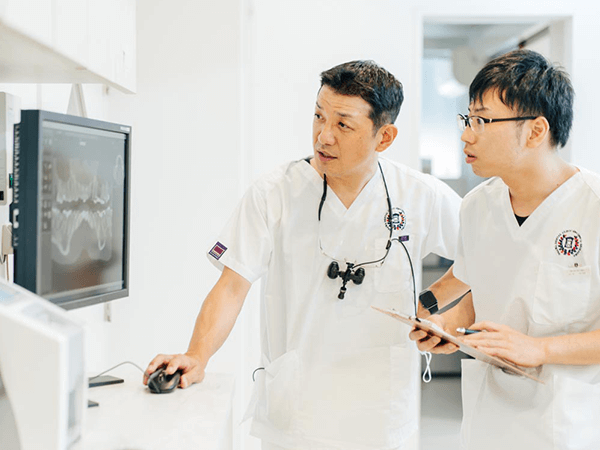

インプラント治療では、チタン製の人工歯根を埋め込みます。チタンは金属でありながら生体親和性が高く、骨と結合する性質があります。顎の骨と結合することで、天然歯と変わらない自然な噛み心地を長期的に実現します。

一般的に、人工歯冠の素材には耐久性が高いセラミックが使われます。独特な透明感のあるセラミックは見た目も美しく、天然歯と変わらない審美性があります。また、噛む力がしっかりと顎の骨に伝わるため顎周りの筋力低下や骨の吸収が起こらず、輪郭が変化することを防げるのも大きなメリットです。

1本からでも治療可能

インプラントは、1本からでも治療可能です。ブリッジや入れ歯のように、ほかの歯を支えにしたり削って形を整えたりする必要はありません。最小限の負担で欠損した歯の機能を取り戻すことができます。